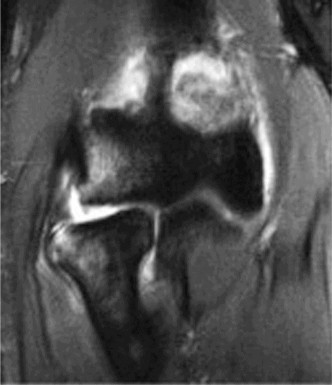

Treat a patient with axillary neuropathy? CASE 24 A 21-year-old, right-hand-dominant, male, college swimmer presents to clinic complaining of gradually worsening right shoulder pain for the past 6 months. He notes that his times at swim meets have been slowing with the onset of the pain but that he is still able to swim through the pain. Physical examination reveals: decreased muscle bulk over the infraspinatus fossa of the right shoulder compared with the contralateral side (shown in Fig. 2–64), full active range of motion, strength 4/5 for external rotation but otherwise normal strength, mild pain with cross-body adduction of the right shoulder, and mild tenderness to palpation over the AC joint. Imaging is shown in Figure 2–65.

Figure 2–64

Figure 2–65

The correct answer is (D). This patient’s atrophy of the infraspinatus muscle leading to weakness with external rotation and with preserved strength in the other rotator cuff muscles is likely due to neuropathic process of the suprascapular nerve at a

point along its course off the upper trunk of the brachial plexus on its way to innervate the supraspinatus and infraspinatus muscles. Choice A is incorrect as rotator cuff tendinitis would not present with muscle atrophy. AC joint arthritis (Choice C), while often presenting with tenderness to palpation over the AC joint and pain with cross body adduction, is also not usually associated with infraspinatus atrophy and would likely present with narrowed joint space or AC joint osteophytes on plain films, unlike this patient. Choice B is incorrect as the patient has full active range of motion, while adhesive capsulitis would more likely present as decreased active and passive range of motion.

You send the patient for an MRI, which is shown in Figure 2–66.

Figure 2–66

The correct answer is (C). The patient’s clinical examination findings of isolated

weakness in external rotation and atrophy of the infraspinatus muscle point to suprascapular nerve entrapment at a location past the exit point for the branch to the supraspinatus muscle. Also, MRI reveals a posterior labral tear with a paralabral cyst that is compressing the suprascapular nerve at the spinoglenoid notch. Choice A, while fitting with the patient’s clinical examination, does not fit with the MRI showing paralabral cyst. Choices B and D are incorrect because entrapment of the suprascapular nerve at the suprascapular notch by scapular body fracture or by the transverse scapular ligament (more common) would lead to weakness/atrophy in both supraspinatus and infraspinatus muscles as the suprascapular notch is proximal to the nerve branch point to the supraspinatus muscle.